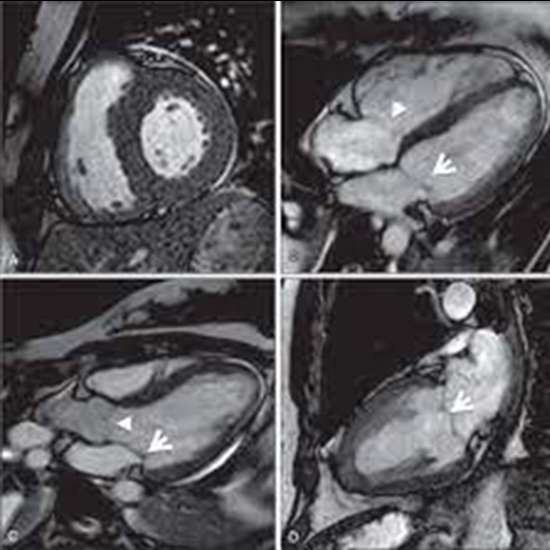

Cardiac MRI (Magnetic Resonance Imaging) is a non-invasive medical imaging technique that can provide the detailed information about the structure and function of the heart.

- Accurate Diagnosis: Cardiac MRI can provide high-resolution images of the heart, which can help in the accurate diagnosis of various heart conditions. It can detect abnormalities in the heart’s structure and function, such as heart-valve problems, heart muscle damage, and blockages in the blood vessels.